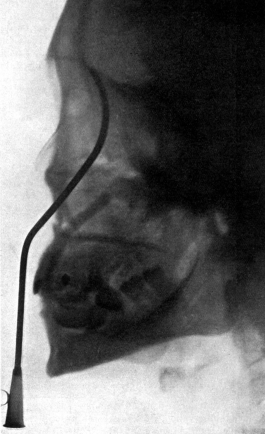

| 267. | Skiagram showing an Angular Tracheotomy Tube in the Trachea | 518 |

| 334. | Radiograph to show the Value of the Röntgen Rays | 639 |

| 335. | Radiograph showing Canula in the Frontal Sinus | 639 |

| 343. | Radiograph of the Sphenoidal Sinus | 653 |

| 344. | Radiograph of the Sphenoidal Sinus | 653 |

| 345. | Catheterizing the Sphenoidal Sinus | 654 |

| 347. | Radiograph showing a Probe in the Sphenoidal Sinus | 657 |